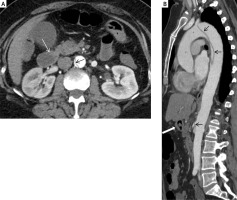

Figure 2

Thickening of duodenal wall (white arrow) and dissection of the abdominal aortal wall (black arrow)